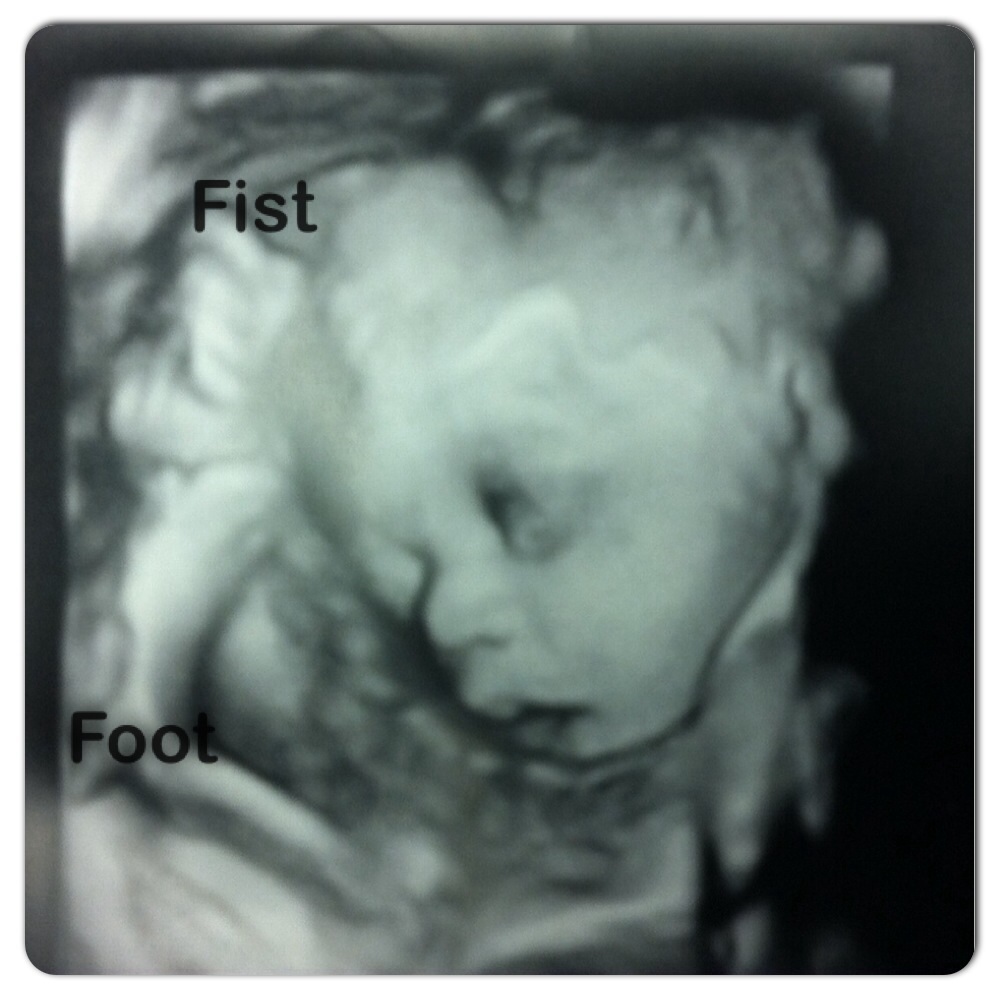

• mindfulturkey I'm not due until November 22 but my baby girl is already over 5 lbs. My doctor is keeping a watch on me because I may also be developing preeclampsia among other things. I pray that I'm not. I'm feeling I should be getting ready especially with these turn of events plus the baby doesn't seem to want to be where she is...contractions, contractions and more contractions.